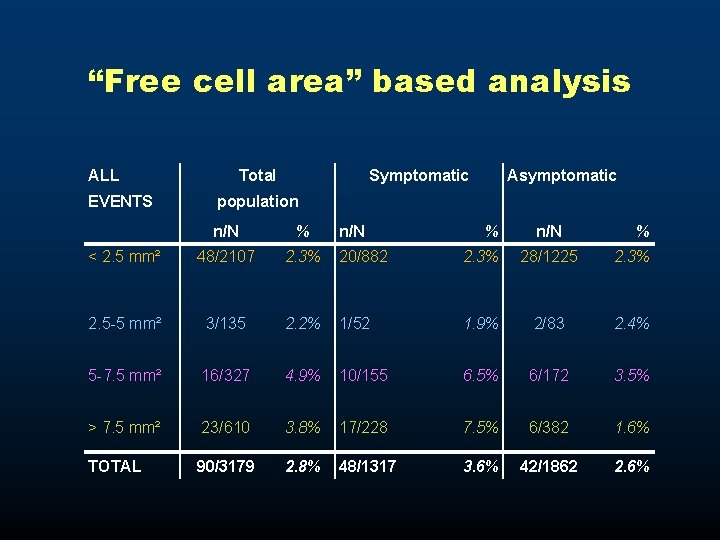

“Free cell area” based analysis ALL EVENTS Total Symptomatic Asymptomatic population n/N % < 2. 5 mm² 48/2107 2. 3% 20/882 2. 3% 28/1225 2. 3% 2. 5 -5 mm² 3/135 2. 2% 1/52 1. 9% 2/83 2. 4% 5 -7. 5 mm² 16/327 4. 9% 10/155 6. 5% 6/172 3. 5% > 7. 5 mm² 23/610 3. 8% 17/228 7. 5% 6/382 1. 6% TOTAL 90/3179 2. 8% 48/1317 3. 6% 42/1862 2. 6%